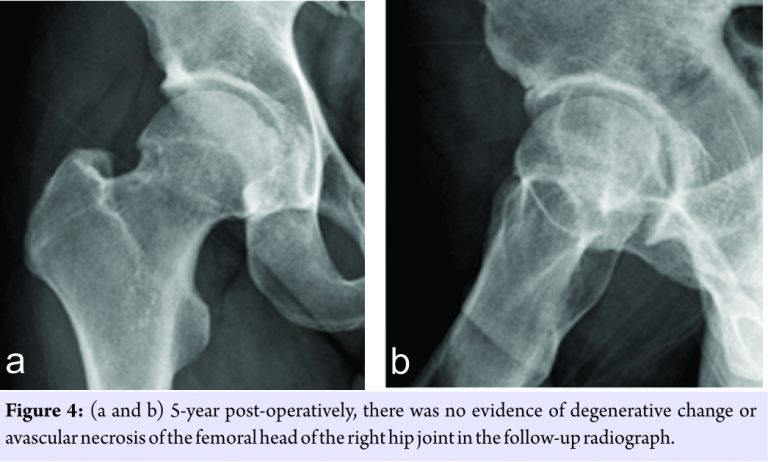

Histologic study revealed characteristic findings of Milgram Stage II synovial osteochondromatosis. The patient has been followed up for 5 years. Subjectively, he has no complaint and full motion of the operated hip joint. Harris hip score improved from pre-operative 60–94 points at the time of the latest follow-up. He plays volleyball and softball regularly without any problem. The latest follow-up X-rays showed clear a right hip joint without evidence of osteoarthritis or avascular necrosis of the femoral head (Fig. 4).